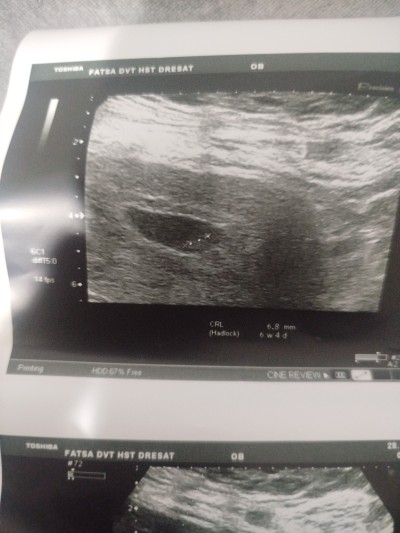

kese şeklıne gore cinsiyet tahmini ne ola bilir

Gebelik haftası 7+4